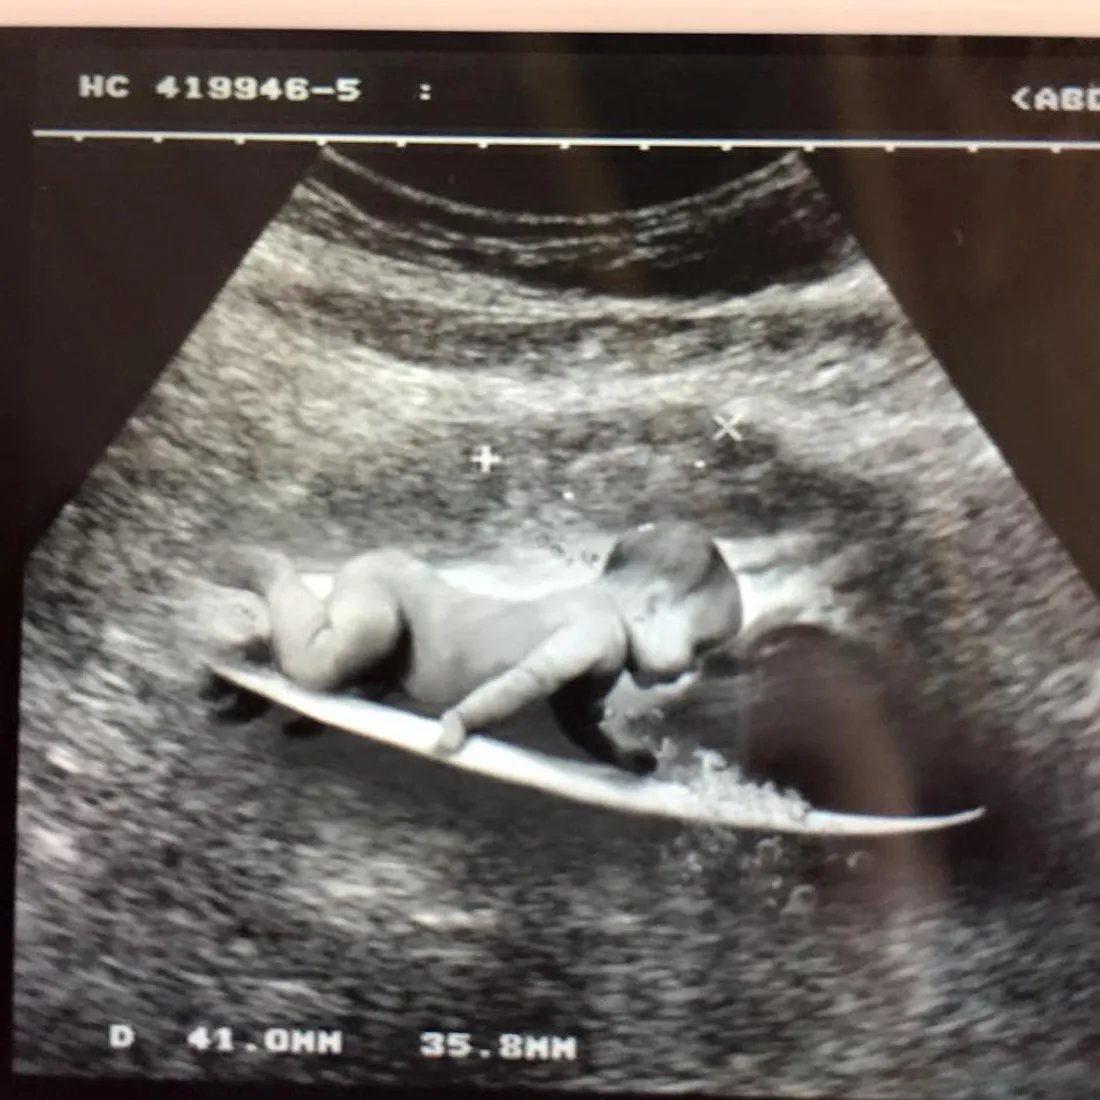

La star de la chanson canadienne attend un bébé ! Natasha St-Pier est enceinte de son premier enfant et sera maman pour la première fois en 2015, une bonne nouvelle que l’épouse de Grégory Quillacq a partagée avant-hier sur Facebook. « Grégory se joint à moi pour vous annoncer l’arrivée cette année d’un surfeur ou d’une surfeuse de plus dans la famille ! », a-t-elle écrit en légende d’une photo d’une échographie originale.